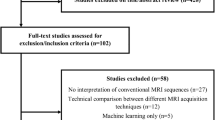

From November 2006 until May 2013, a total of 352 consecutive adult patients with a histopathologic diagnosis of diffuse glioma were identified based on our clinical database. Of these, 87 diffuse glioma grades II and III were diagnosed histopathologically as oligodendroglioma, oligoastrocytoma, or astrocytoma, classified according to the 2007 WHO Classification of Tumors of the CNS, were selected. Molecular genetic status with respect to 1p19q codeletion was available for all patients and met the following inclusion criteria: (1) a baseline pretreatment MRI examination from our institution including DSC-MRI and DWI in addition to T1-weighted and T2-weighted images, (2) age > 18 years, and (3) a signed consent. From this group, 71 were included in the final study cohort. The following patients were excluded: (1) incomplete imaging sequences (n = 8), (2) insufficient image quality (n = 6), and (3) previously performed biopsy (n = 2). The patient inclusion and exclusion process is shown in Fig. 1.